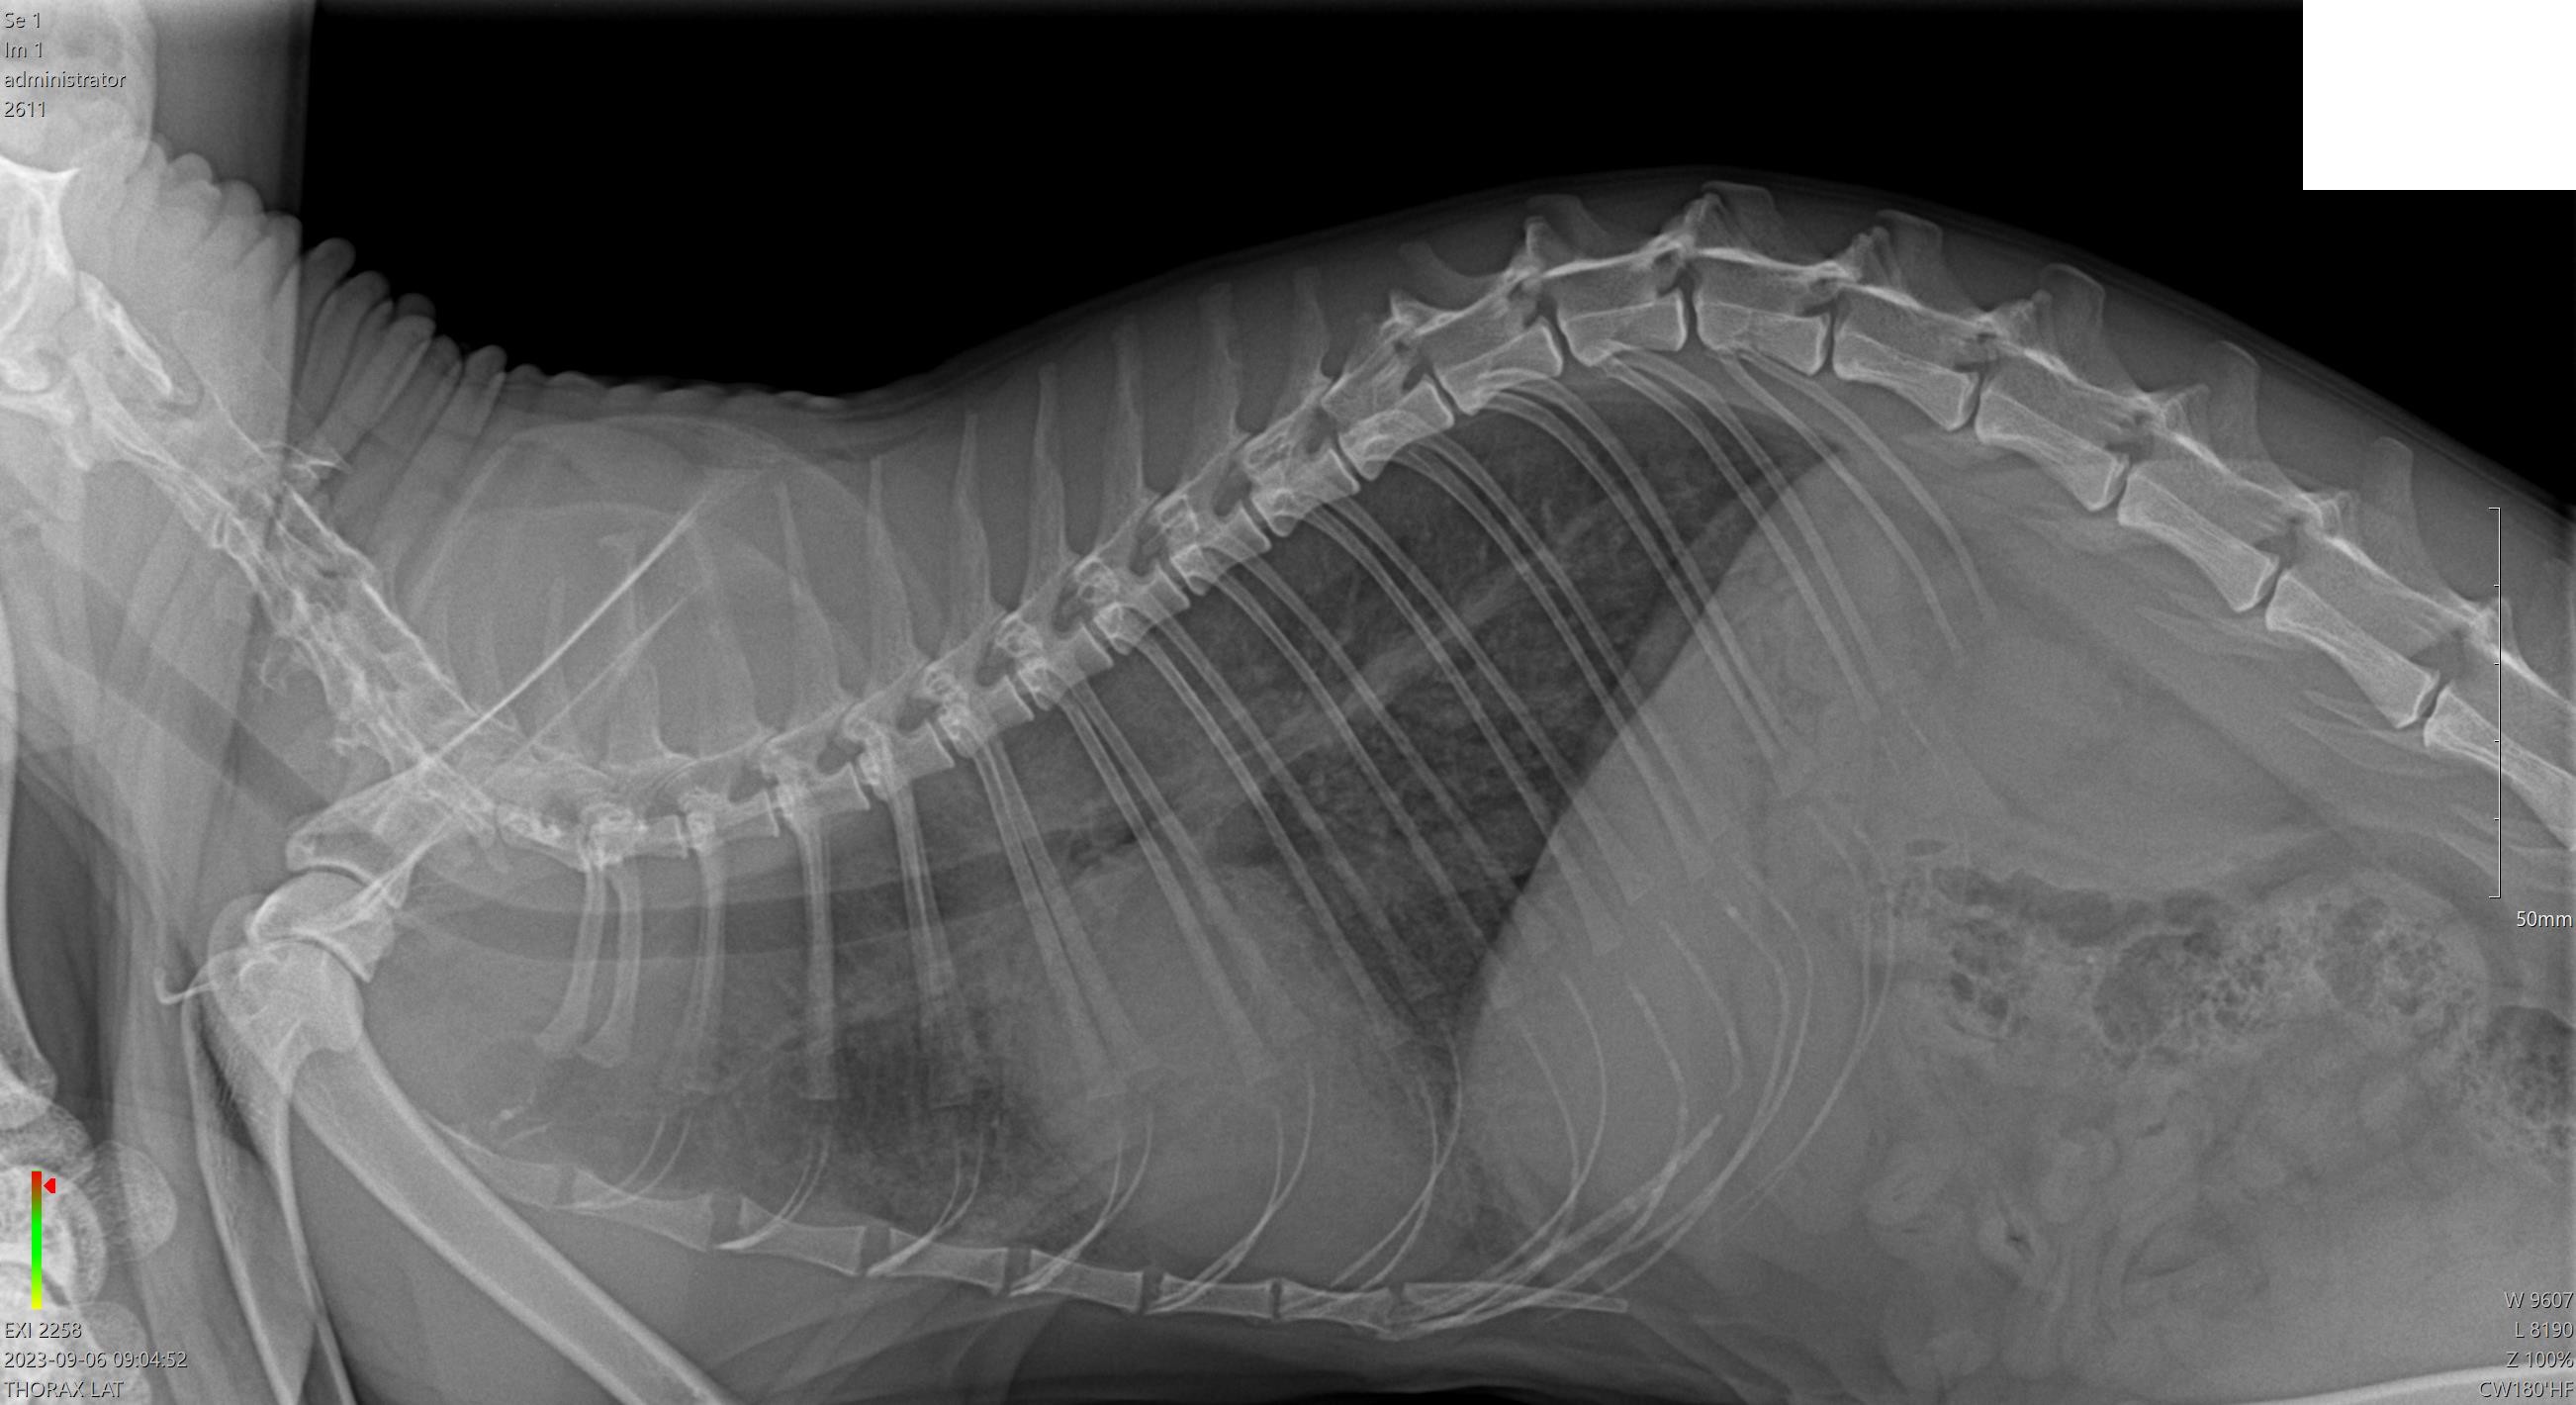

Vážená paní doktorko, vážený pane doktore, děkuji, že provozujete tuto poradnu, je to od Vás moc hezké. Náš kocourek, čtyřapůlletý Sphinx, měl nějakou dobu a především večer záchvaty zrychleného dýchání, případně jakéhosi nedodýchávání, které vypadalo trochu jako astmatický záchvat. Ve středu jsme šli na vyhlášenou veterinu, kde mu provedli rentgen plic (snímky: https://ibb.co/WD3mZNF, https://ibb.co/WD3mZNF - razítko kliniky jsem smazal). Do zprávy doktorka napsala: "srdce tachykardie ze středu, plíce pouze slyšitelné inspirium, bez jiných přidatných šelestů, isotermie, sliznice a spojivky růzové, MU submand. nezvětšené, abdomen prohmatný, nebolestivý na RTG bronchiální plicní vzor susp. kočičí astma / počínající bakt. pneumonie. Pravděpodobně skončí bronchoskopií s BALkou - bez odhadu - odběr BAL na cytologii a kultivaci, nedávám zatím atb, aby se to nepřekrylo Před endoskopií doporučeno proBNP a celkové krve, event. nález eosinofilů v hematologii, rodiče na HCM testovaní, negtivní a vyšetření vzorku trusu" a předepsala Loxicom a Plerasan. V neděli se stav kočičky zhoršil a v noci jsme jeli na pohotovost do jiné kliniky. Na rozdíl od předchozí kliniky, zde hned první podezření byla nemoc srdce a s tím související voda na plicích. Lékař zkusil kortikoidy, kdyby přeci jen šlo o astma. Bohužel za další hodinu se stav kočičky prudce zhoršil a my ji pak viděli umřít trýznivým způsobem. Ano, byla to voda v plicích. Hodně vody v plicích. Dávání kyslíku bylo zbytečné, náš malý miláček se utopil. A má otázka teď je, zda to v tu středu šlo poznat, třeba z těch rentgenů, zda ta medikace dávala nějaký smysl a zda našeho miláčka šlo zachránit. Nevrátí nám ho to, ale máme ještě jednu kočičku a já bych rád věděl, zda tomu pracovišti vůbec můžu důvěřovat. Předem Vám moc děkuji a přeji hodně uzdravených zvířátek.

Dobrý den. Podle vámi popsaných klin.příznaků a dle přiloženého RTG snímku,se domnívám ,že došlo u vaší kočičky k srdečnímu selhání, bohužel zřejmě v konečném stádiu. Myslím si, že v tomto stádiu, ji už nešlo zachránit. S pozdravem MVDr Jančík.